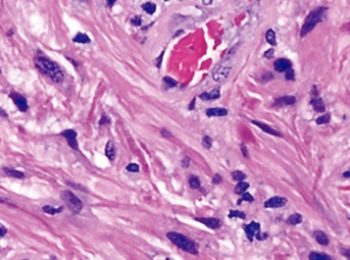

Breathing New Life

Northwestern Medicine team provides life-saving cancer treatment to expectant mother.